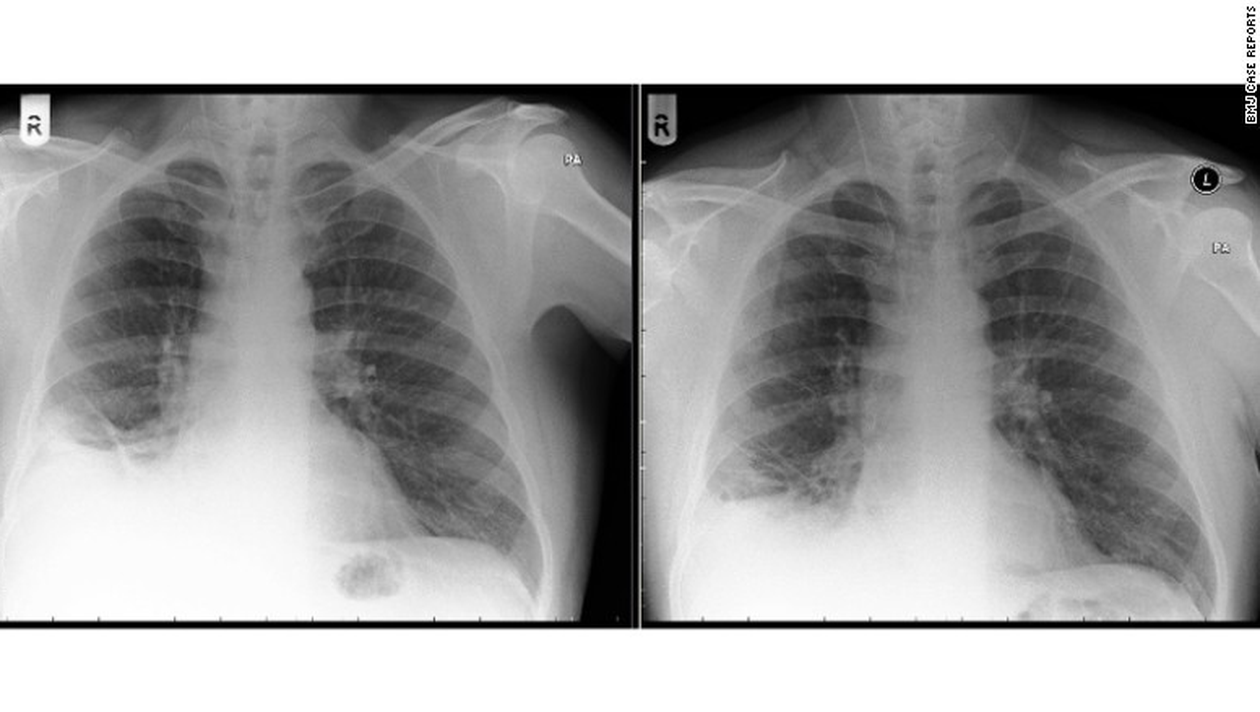

Un barbat in varsta de 50 de ani s-a prezentat la doctor cu dureri in piept si o tuse care nu-i mai dadea pace.

Problemele medicale ale pacientului au debutat pe cand avea 46 de ani. Doctorii care l-au consultat au crezut ca e un fel de cancer la plamani si ca trebuie operat.

In momentul in care l-au deschis, au ramas muti de uimire cand in locul unei formatiuni canceroase au descoperit o…